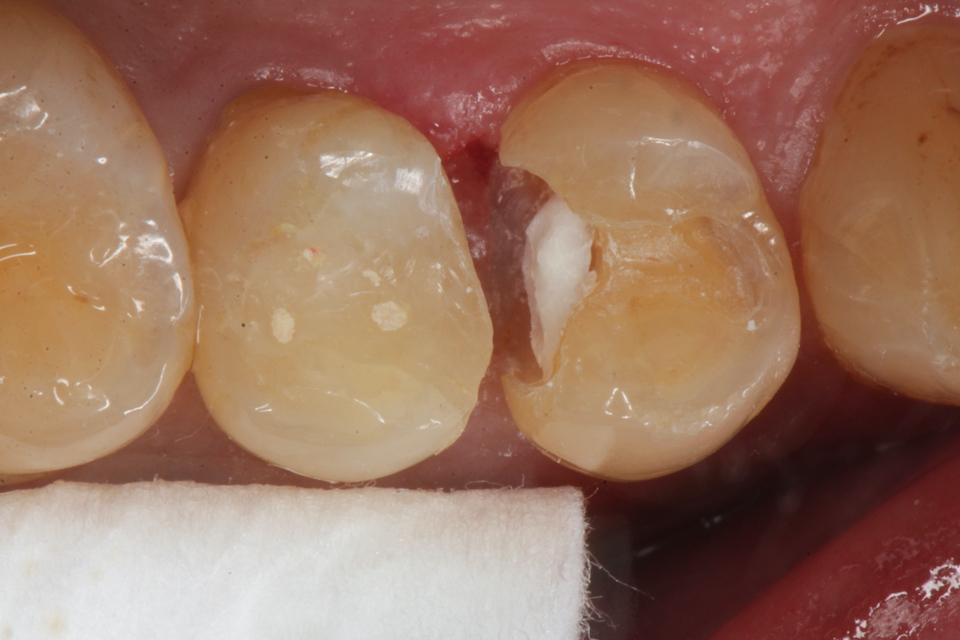

50代男性、右上45、インレー破折後の2次カリエス、咬合性外傷

露髄ギリギリなのだが、自覚症状はない。虫歯がある程度進むと染みたり痛みを感じにくくなる。それは虫歯は水素イオンの電導性がないからだ。水素イオンが歯髄の神経に到達すると痛みを感じるのだが、水素イオンの伝導は歯の主成分のハイドロキシアパタイトだけにしか起こらず、ハイドロキシアパタイトが壊れてしまった虫歯には水素イオンが伝導しない。

咬合性外傷があるとスレあとが着く。